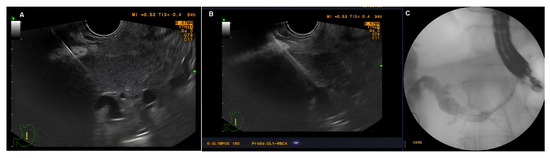

4.2.5. PTBD

Ultrasound (Hitachi Aloka alpha 7, Tokyo, Japan) examination was conducted and the desired duct was selected. In general, as peripheral a duct as possible was selected to reduce the risk of bile leakage. Puncture of the extrahepatic ducts was avoided. The needle direction was oriented towards the hilum of the liver to alleviate subsequent guidewire advancement and manipulation. The access point of the needle could be either transabdominal or intercostal. Transabdominal approach was the first choice and presumed safer. An 18Ga puncture needle (Urothech GmbH, Rohrdorf, Germany) was used. Upon puncturing the bile duct, the stylet was removed. Spontaneous leak of bile was awaited to confirm correct positioning; if this was not observed, then gentle suction was with a 5 mL syringe prefilled with 2 mL of 0.9% NaCl was performed. Only a small amount of bile was aspirated to avoid rapid decompression of the biliary tree and consequent loss of position. If bile leakage did not occur, cautious repositioning of the needle under US guidance was performed with repeated aspiration. In case of failure, the needle was retracted and the manipulation repeated. In rare cases with suspected purulent cholangitis, cautious irrigation with saline was performed prior to reaspiration. Once in the target duct, cholangiography was performed. A C-arm machine (Philips BV Pulsera C-arm, Philips, Best, The Netherlands) was used for fluoroscopy guidance. Only mild opacification of the bile duct was conducted to be used as a roadmap, with overextension of the biliary tree generally considered unfavorable.

Once fluoroscopic assessment of biliary anatomy was conducted, a 0.035 J-type Lunderquist guidewire (Urothech GmbH, Rohrdorf, Germany) was introduced in the biliary tree. Next, a dilation of the fistulous tract was performed with 7fr and 10fr plastic dilators (Urotech GmbH, Rohrdorf, Germany). Upon dilation, a 7fr or 10fr (Urotech GmbH, Rohrdorf, Germany) plastic “pig tail” drainage catheter was advanced along the guidewire and positioned as distally as possible in the bile ducts. Drainage catheters with locking mechanism (only 10fr available) were preferred. Eventually, the drain was fixed to the skin with two sutures. Trans-drainage cholangiography was performed at the end of the procedure to verify the position and exclude bile leakage in the peritoneal cavity or inadvertent puncture of a blood vessel.